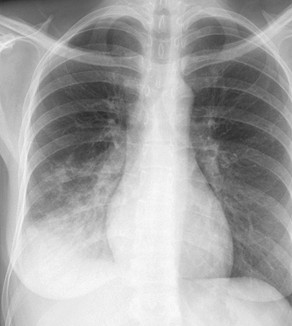

突然ですが、レントゲンクイズを出題します。画像の所見を読んで、離床の注意点を説明してください。

[レントゲンクイズの解答例]

右横隔膜シルエットサイン陽性、右下肺野のすりガラス影とエアブロンコグラムを認めることから、右下葉の肺炎が疑われます。炎症パラメータと呼吸状態をアセスメントして、悪化傾向のときには、離床のを一度見合わせて、合併症を予防するADLレベルの活動にとどめます。